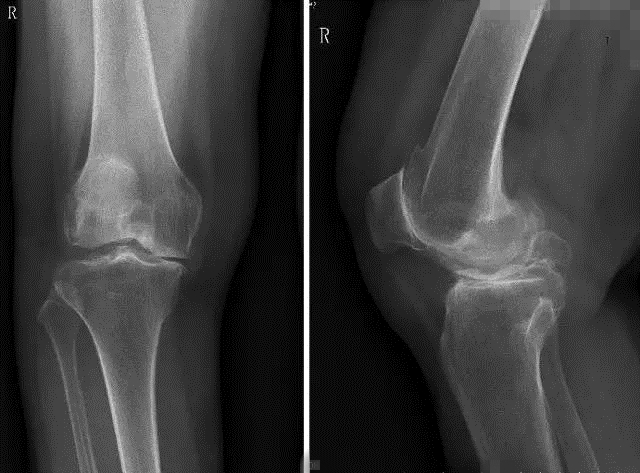

术前患者膝关节正侧位平片